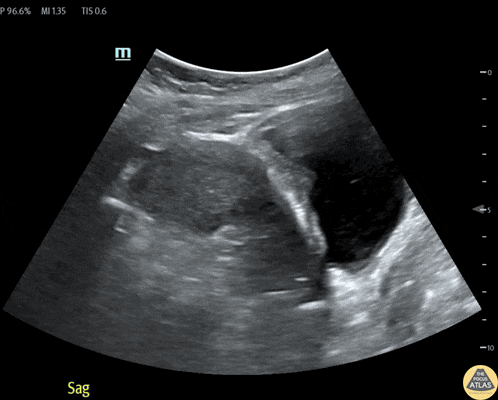

OB/Gyn - Caesarean Section Scar Ectopic Pregnancy

32 year old female at 8-9 weeks gestation by LMP referred to the ED for pregnancy of unknown location. She reported 1-2 weeks of mild pelvic cramping and vaginal spotting. Bedside trans-abdominal imaging demonstrated a round, heterogenous structure without a clear yolk sack or fetal pole, but with several hallmarks of caesarean scar ectopic pregnancy: position in the anterior uterine wall; in the lower (closer to the cervix) half of the uterus; bulging into the neighboring bladder; with thin interposed myometrium. After confirmatory formal ultrasound, she was admitted for methotrexate termination, which proved successful. Contributors: Nicholas Maurer, MD, MPH (PGY-1); Megan Chenworth (PGY-3) Emergency Medicine, Northwestern McGaw Medical Center